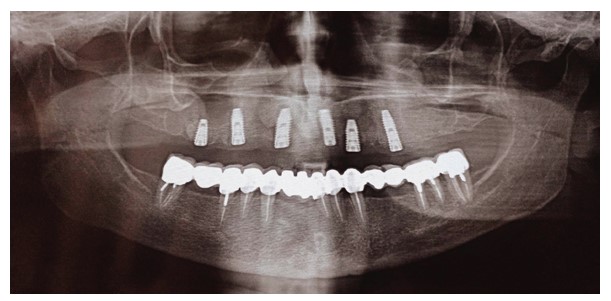

A 62-year-old female patient presented for maxillary rehabilitation with an implant-supported fixed prosthesis. Clinical examination revealed a failing conventional fixed partial denture extending from tooth #14 to #21, exhibiting significant gingival recession and radiographic evidence of periapical pathology. Preoperative cone-beam computed tomography (CBCT) using a Planmeca ProMax 3D unit demonstrated a well-defined radiopaque lesion measuring 1.5 × 1.3 cm adjacent to tooth #16, with a buccal-palatal width of 8.2 mm and bone density measuring 1250 Hounsfield units (Fig. 1).

Preoperative OPG showing a radiopaque lesion on the right posterior maxilla.

After six months, the implants were exposed, healing abutments were placed, and prosthetic procedures began (Figs. 3 and 4). The RFA of the implant within the lesion revealed a measurement of 83.

OPG 6 months after surgery showing the success of the dental implant placed within the osteosclerotic area.